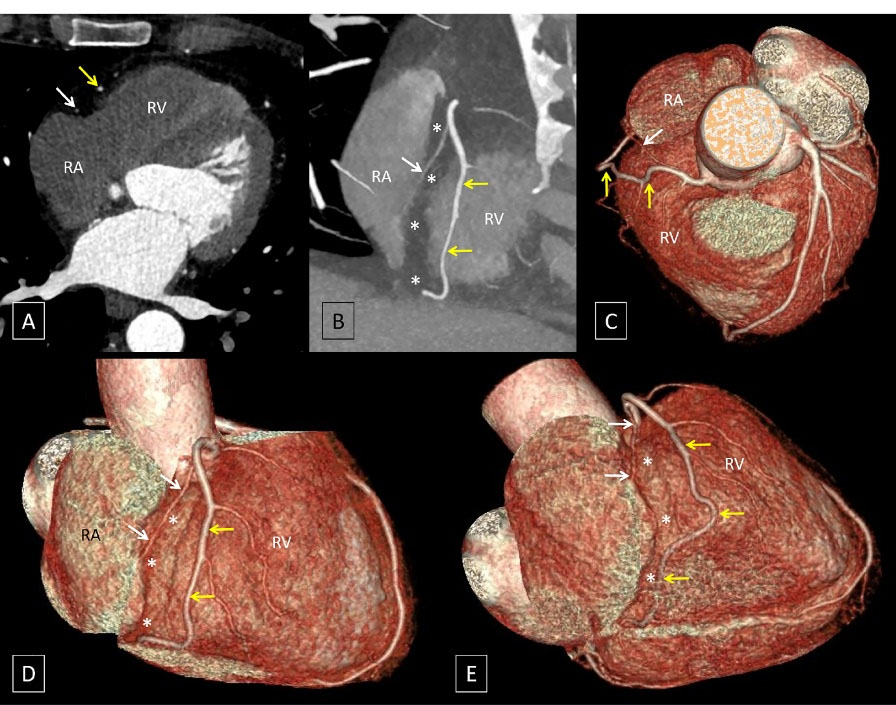

A 53-year-old man with complaints of atypical chest pain underwent coronary CT angiography to rule out atherosclerotic coronary artery disease (CAD). While no obstructive CAD was seen, an interesting variation in right coronary artery (RCA) morphology was incidentally detected. After origin of the conal artery, the RCA proper was seen dividing into two segments. The posterior branch or the “short RCA” was seen coursing within the proximal part of the right atrioventricular (AV) groove and terminated in the mid-portion of the right AV groove. The anterior branch or the “long RCA” was seen to have a proximal course outside the right AV groove, over the free wall of the right ventricle, where it gave rise to the right ventricular and acute marginal branches before returning to the right AV groove in its distal course (Figure 1).

Oblique axial (A), oblique coronal (B) and volume rendered images (C to E) demonstrate the RCA proper dividing into two branches. The posterior branch (white arrows) courses within the proximal part of the right atrioventricular (AV) groove (indicated by asterisks) and terminates in the mid-portion of the right AV groove. The anterior branch (yellow arrows) has a proximal course outside the right AV groove, over the free wall of the right ventricle (RV), where it gave rise to the right ventricular and acute marginal branches before returning to the right AV groove in its distal course. [RA: right atrium]